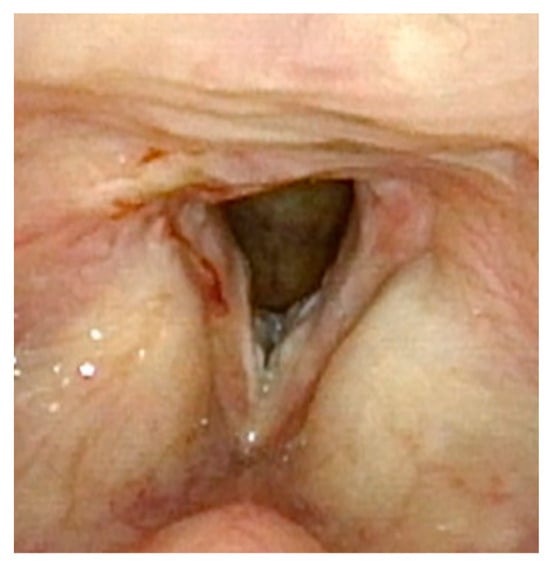

Figure 1 demonstrates a patient who had too aggressive anterior commissure laser treatment. A consequence of this was a very large anterior glottic web. Should this be encountered, the web may be lysed in the midline and steroid-injected (Figure 2). If the web is not the full thickness of the vocal folds, it should be cut with cold steel to help prevent the return of the web during healing. Once healed the web should be significantly improved (Figure 3). Consideration should be given to the dilation of the glottis following lysis.

Figure 3.

Three months post-op following laser ablation of laryngeal papilloma and lysis of anterior glottic web. The majority of the anterior glottic web is resolved, but there is already regrowth of papillomas.